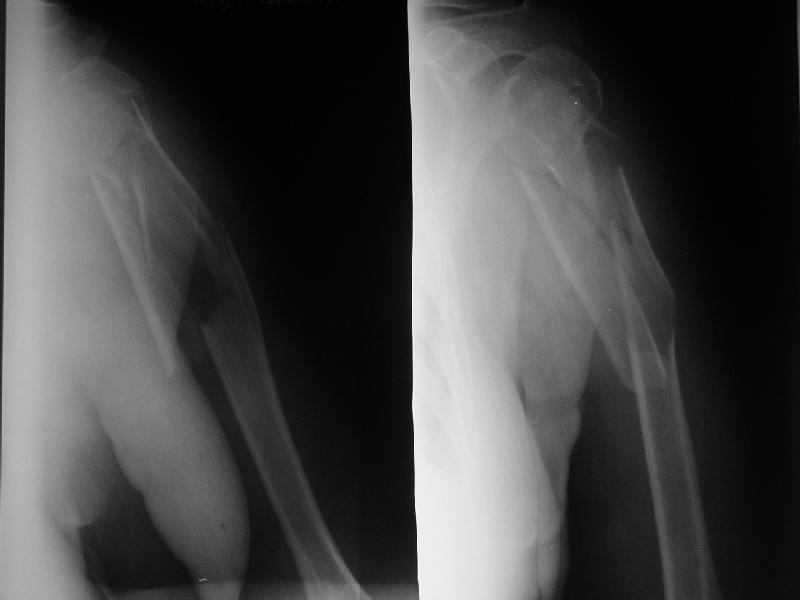

Re: Оскольчатый перелом плеча

Доминирующая ли рука и какая профессия?

Если выбор на интрамедулярный штифт, я бы сделал КТ головки, информация необходима для определения вовлечения головки в перелом, имеется опасность

расколочения и для ориентира расположения блокирующих шурупов.

Другой вариант, небольшой гипс на локтевой сустав как груз для тракции, повязкой за кисть выше-вниз можно контролировать сгибание и разгибание на место перелома, небольшая отводящая подушка в живот (у женщин молочная железа в зоне перелома

создает варус)сделать ренген снимки через одну недели. Перелом низкоэнергетический, может быть, без операции обойдется.

"Рука не доминирующая, но тоже нужна" - А.Н. Челноков. Больная уже лечилась консервативно в гипсовой повязке и на вытяжении, в настоящее время настаивает на оперативном лечении.

Есть и другие косые снимки, на которых не определяется вовлечение головки, если успеем - сделаем КТ. Спасибо за интерес к нашему случаю.

Ув. коллеги. Интересно, насколько разрушена головка, особенно ее артикулирующая поверхность, может для начала сделать КТ головки.

На счет операции - стоит ли ее вообще делать, куда Вы собираетесь забить стержень, на расколете ли головку, если она еще целая. В любом случае Вы

не добъетесь стабильной фиксации, прийдеться иммобилизировать где-то на месяц. Вопрос: какова будет функция после травматичной операции, а она

имеенно таковой будет и последующей иммобилизации. ВЧКДО сделать не получиться - не за что зацепиться.

> Ув. коллеги. Интересно, насколько разрушена головка, особенно ее

> артикулирующая поверхность, может для начала сделать КТ головки.

По нескольким снимкам в чуть разых проекциях она не фрагментирована. А если и были трещины, за прошедшие 3 недели они "слиплись", очевидно. А КТ если сделаем - еще можем испугаться увиденного :-)